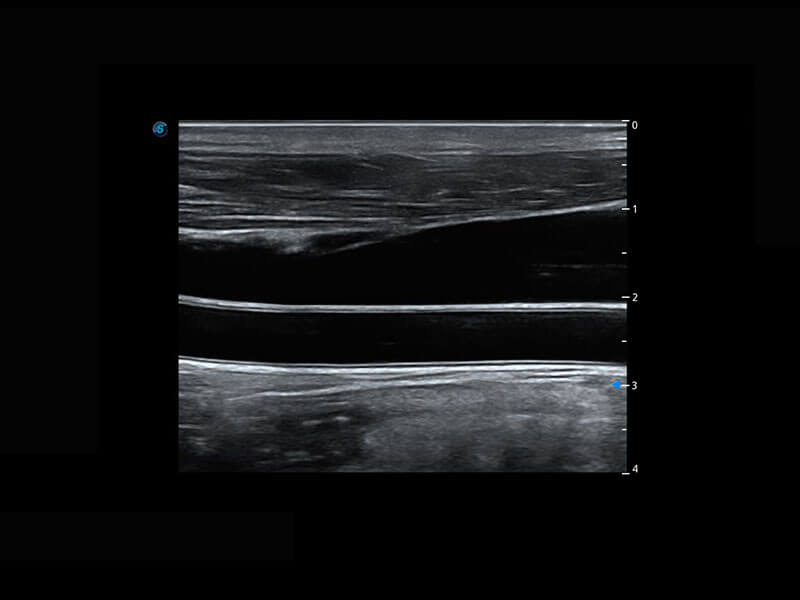

P60搭载宽频带线阵探头、宽景成像、弹性成像技术,为您提供乳腺应用方案。P60支持高频相控阵探头、线阵探头、腹部高频探头、腹部微凸探头等,丰富的探头群搭载敏感的彩色血流成像,适用于新生儿多种脏器检测要求,满足新生儿筛查需求。

乳腺导管癌

乳腺癌显微血流

新生儿脊髓圆锥

新生儿心脏